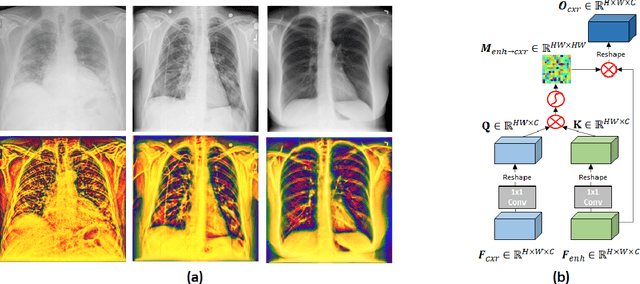

Under the global COVID-19 crisis, accurate diagnosis of COVID-19 from Chest X-ray (CXR) images is critical. To reduce intra- and inter-observer variability, during the radiological assessment, computer-aided diagnostic tools have been utilized to supplement medical decision-making and subsequent disease management. Computational methods with high accuracy and robustness are required for rapid triaging of patients and aiding radiologists in the interpretation of the collected data. In this study, we propose a novel multi-feature fusion network using parallel attention blocks to fuse the original CXR images and local-phase feature-enhanced CXR images at multi-scales. We examine our model on various COVID-19 datasets acquired from different organizations to assess the generalization ability. Our experiments demonstrate that our method achieves state-of-art performance and has improved generalization capability, which is crucial for widespread deployment.